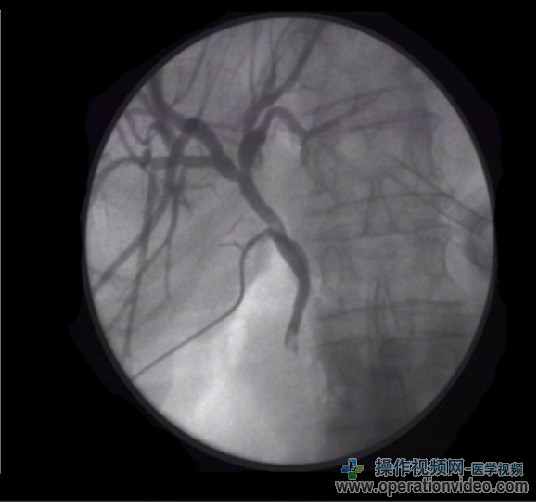

术中胆道造影执行三个步骤:

1。影像学指导下的胆管注入几毫升稀释的对比(50%稀释)。这是必要的,以确保没有气泡在注射设定的“生物多样性公约”可以用石头混淆,因为气泡。如果静态图片正在采取的第一个被检测到石头的点睛之笔。

2。继续进行,直到一个完整的胆管造影得到的染料喷射。头低脚高的位置,可促进肝内胆管混浊。第二个静态图像,在这一点上。

3。在低压下进入十二指肠通过染料应确认由三分之一的X光片。

如果有胆管造影期间整个胆总管可视化不足,温和的压力可以与仪器放置在前端部分的CBD,以鼓励足够灌装和划分。如果X线透视正在被使用,则可以得到图像动态同时注入对比度。 |